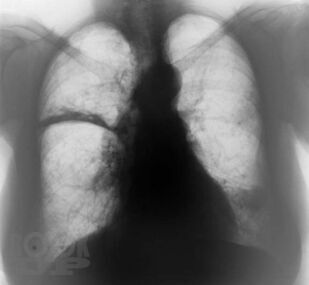

Клинико-рентгенологическая диагностика болезней органов дыхания

Основу данной книги составил архив клинико-рентгенологических наблюдений, собранный авторами в течение ряда лет. Авторы не стремились к подробному описанию клинико-рентгенологической диагностики многочисленных заболеваний бронхолёгочной системы. Материал излагается кратко, почти тезисно и отражает наиболее важные сведения об основной патологии органов дыхания. Цель книги — отражение вопросов клинической картины и рентгенодиагностики распространённых бронхолёгочных заболеваний в условиях муниципальных учреждений здравоохранения с позиции врача общей практики. Предназначено для терапевтов, семейных врачей, студентов медицинских вузов.